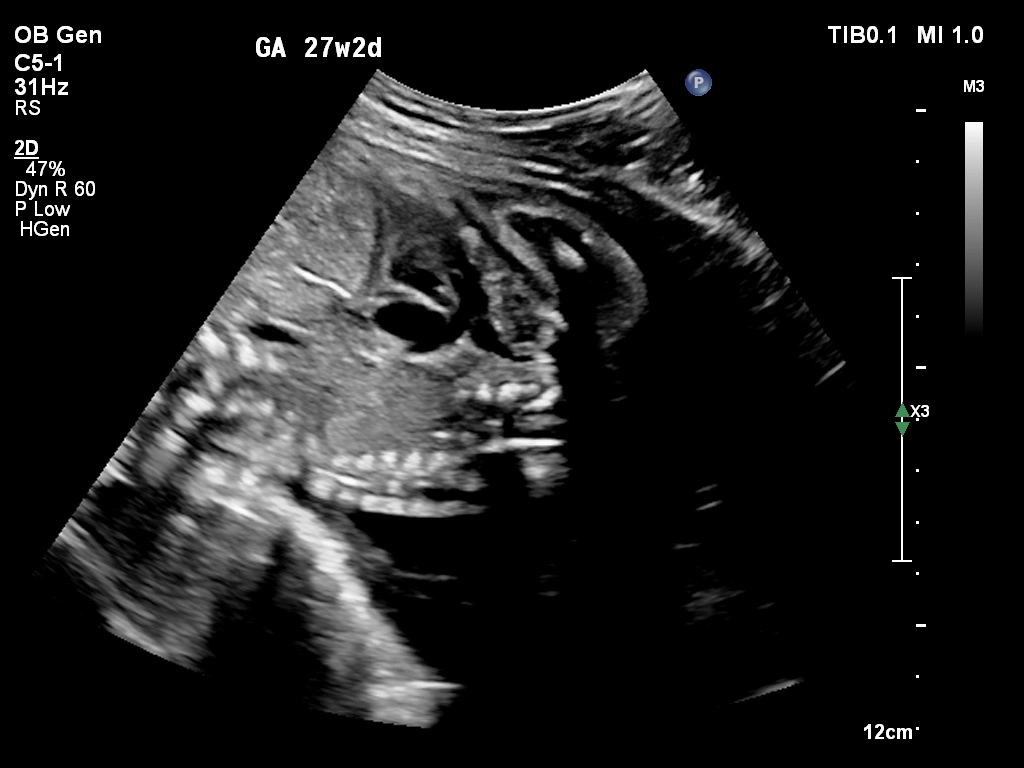

🔹 Anomaly Scan (Level II Ultrasound)

Anomaly Scan is a detailed ultrasound performed during pregnancy (usually between 18 and 22 weeks) to check the baby’s development. It helps detect structural abnormalities in the brain, heart, spine, kidneys, and other organs. This scan ensures your baby is growing normally and helps doctors identify any potential complications early. If you are looking for a reliable anomaly scan in Kathmandu, an early and accurate diagnosis is essential for a safe pregnancy.